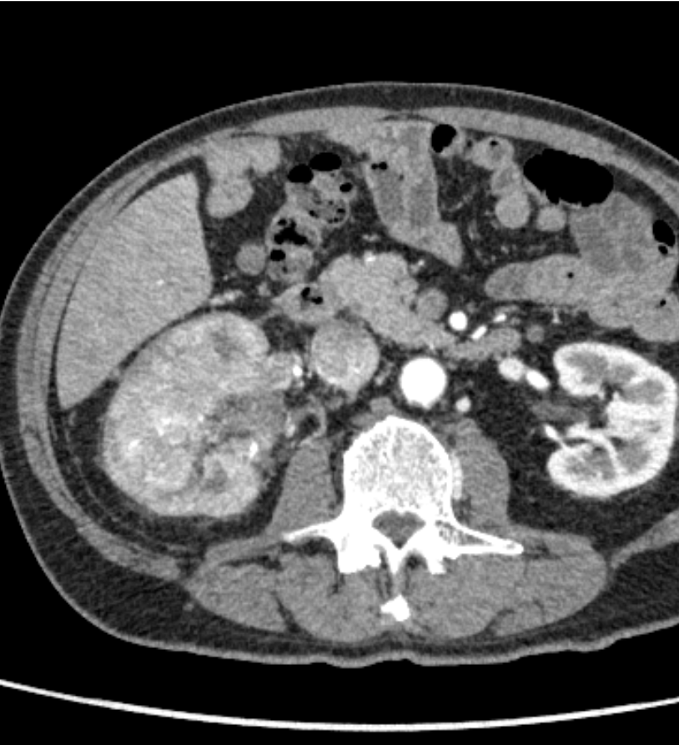

右腎には、実質を置換性に広がる早期濃染とwashoutを示す腫瘍を認め、腎細胞癌と考えられた。腫瘍は腎静脈を経て下大静脈に進展し横隔膜レベルに達していた。また左腎動脈には低造影域を認め、肺動脈腫瘍栓と考えられた。

腎腫瘍の診断において、ダイナミック造影CTはその組織型の推定に有用である。腎腫瘍の多くの割合を占める通常型(淡明細胞型)腎細胞癌は、早期相で周囲の腎皮質と同程度に濃染し(早期濃染)、後期相では周囲に比してやや低造影を示す(washout)ことが特徴である。さらに、腫瘍増大に伴い、本症例のように腎静脈や下大静脈へ進展が見られやすいのも特徴の一つと言えるだろう。また、本症例では腎動脈に塞栓を疑う低造影域を認めた。多くは血栓塞栓であり、その場合は原因となる下肢静脈血栓の有無を検索する必要がある。しかし、本症例では肺動脈内病変には斑な造影効果を認め、FDG-PET(非提示)では集積像を示した。静脈内進展を伴う腎腫瘍の存在と合わせて肺動脈腫瘍栓と診断した。肺動脈塞栓を認めた場合には、血栓以外の可能性についても一考することが大切である。